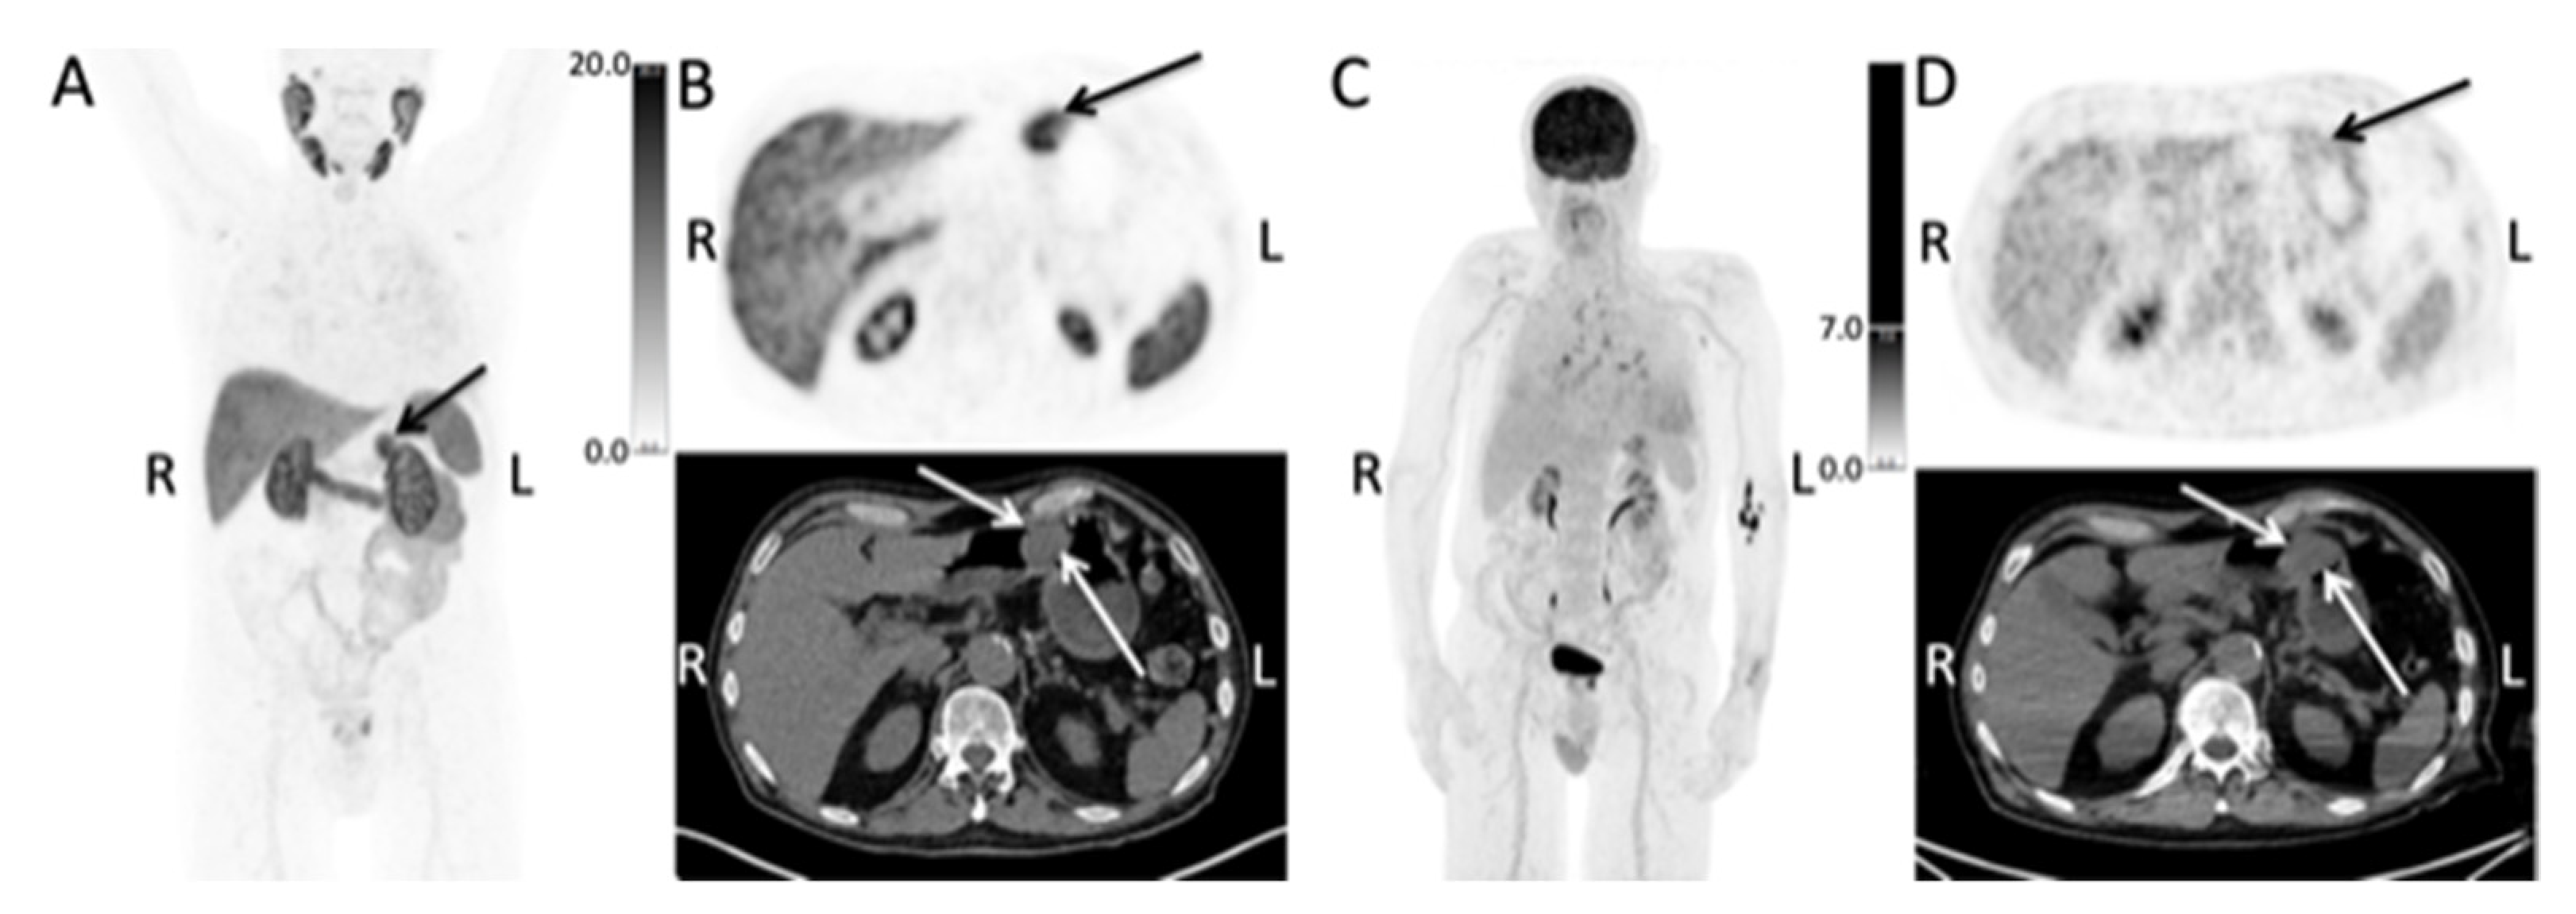

Figure 1.

The maximum intensity projection (MIP) of the F-18-PSMA-1007 PET/CT (A) show a PSMA-positive lesion located in the upper abdomen (arrow) (R, right side; L, left side). Transaxial images of the of the F-18-PSMA-1007 PET/CT (B) show the PSMA-positive polyp in the body of the stomach, as indicated by the arrows. The maximum intensity projection (MIP) (C) and transaxial images (D) of the prior F-18-FDG PET/CT showed low FDG uptake in the polyp (arrows).

One month later, the patient was referred for primary staging with F-18-PSMA-1007 PET/CT. The scan showed localized disease within the prostate with no sign of involvement of the seminal vesicles, lymph nodes or bones. Additionally, the scan showed a PSMA-positive lesion (SUVmax = 21) in the body of the stomach on the greater curvature, correlating to a 35 mm polyp located close to the pylorus (Figure 1, Panel A and B).

A 76-year-old man with newly diagnosed prostate cancer. The PSA level was 13 μg/L. Gleason 4 + 4 = 8 was found in 11 of 12 biopsies, alongside a cT2c tumor and a prostate volume of 20 ccm. About one month prior to the diagnosis, the patient was referred for an 18-F-FDG-PET/CT for unspecific symptoms, moderate elevation of C-reactive protein level and fever in order to locate infection sites or active inflammation, with the secondary aim of ruling out an underlying cancer. The patient had a medical history of methotrexate-treated seropositive rheumatoid arthritis. The F-18-FDG PET/CT showed localized uptake in the prostate and reactive mediastinal lymph nodes, and low FDG uptake (SUVmax 2.8) in a 35 mm polyp in the body of the stomach (Figure 1, Panel C and D). The latter was not mentioned in either the CT or PET report.